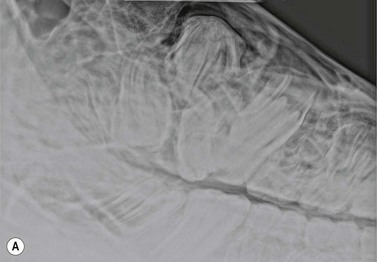

image image

Fig. 13.22 (A & B) A blunt metallic probe placed into a cutaneous discharging tract and secured with radiolucent tape can provide strong evidence as to which tooth is infected in cases of suspected periapical infection.

Fig. 13.23 Lateral oblique radiographs with a blunt metallic probe in place in cases of periapical infection with discharging cutaneous tracts involving the mandibular (A) and rostral maxillary (B) cheek teeth.